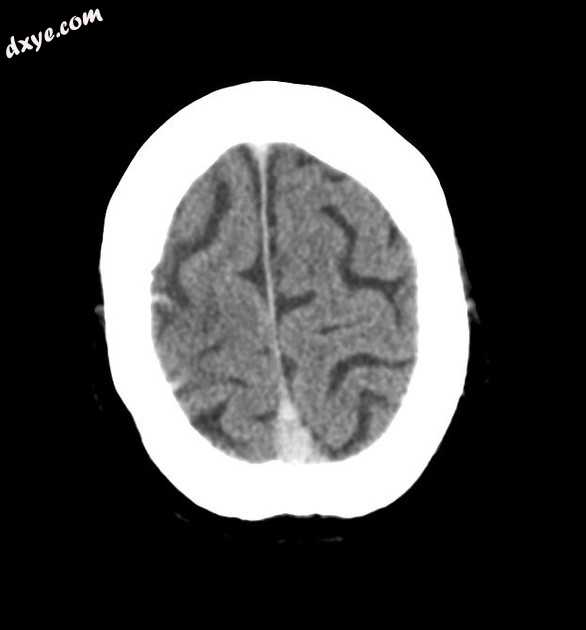

右额叶可见出血。

右侧皮层浅静脉(Trolard 静脉)、上矢状窦、直窦高密度,符合致密静脉征。

CT结果显示出血性病灶伴致密静脉征,提示出血性静脉梗塞。